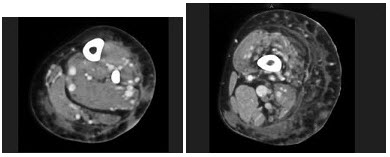

6、单项选择题

患者,男,50岁,右上腹痛伴黄疸,超声体检发现腹腔多个液性暗区。CT图像如下,最可能的诊断是()

A.腹腔囊肿

B.先天性胆管囊肿Ⅳ型

C.腹腔皮样囊肿

D.肝囊肿

E.胰腺囊肿